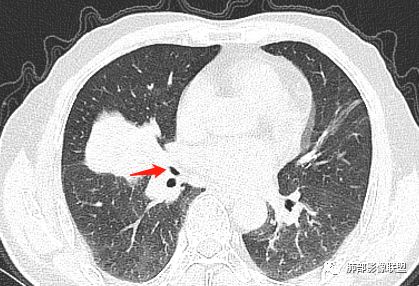

主病灶在中叶,但是左肺舌段叶有条索影,陈旧病变。蓝色箭头支气管受压,是淋巴结肿大

主病灶在中叶,但是还有结节状病变在下叶

是这样长过去的吗?

下面我们看看支气管都在吗?

内侧段是通畅但是受压的

外侧段一开始狭窄

但是远端通畅,所以我认为支气管都没有堵塞,不太可能是鳞癌

边缘还有多发小灶